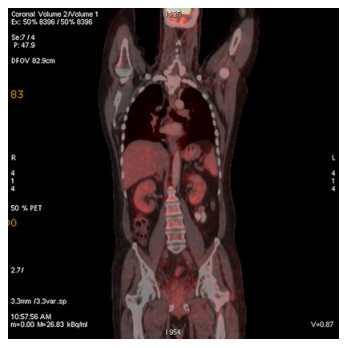

Abstract: Rectal malignancy is usually symptomatic due to its location, and most of the time presents with pain and bleeding due to its growth and ulceration. It is difficult to identify the primary as carcinoma or lymphoma based on symptoms only, as both have a similar presentation. As it presents the rarest form of histology, non-Hodgkin's lymphoma in the rectum is still difficult to diagnose initially, and its treatment is debatable. We describe the case of a 49-year-old male from Bangladesh with the same presentation. His treatment was delayed for more than a month as immunohistochemistry and staging delayed the final diagnosis. The disease was diagnosed as stage IE with the help of a positron emission tomography (PET)-CT scan, and due to the local progression the patient had a massive rectal bleeding that needed an urgent intervention. Radiotherapy was applied to stop the bleeding. Hypofraction followed by a conventional fraction of external beam radiotherapy (EBRT) with a total of 40 Gy was applied. Post-EBRT digital rectal examination showed no residual except scaring, and a PET scan was also negative for residual disease. Due to uncertainties and lack of any precious guideline, 6 cycles of adjuvant chemotherapy with the R-CHOP schedule were also completed. Without surgery, the combination of EBRT and chemotherapy helped to preserve the organ, and the patient has been disease free for more than 2.5 years since his treatment.